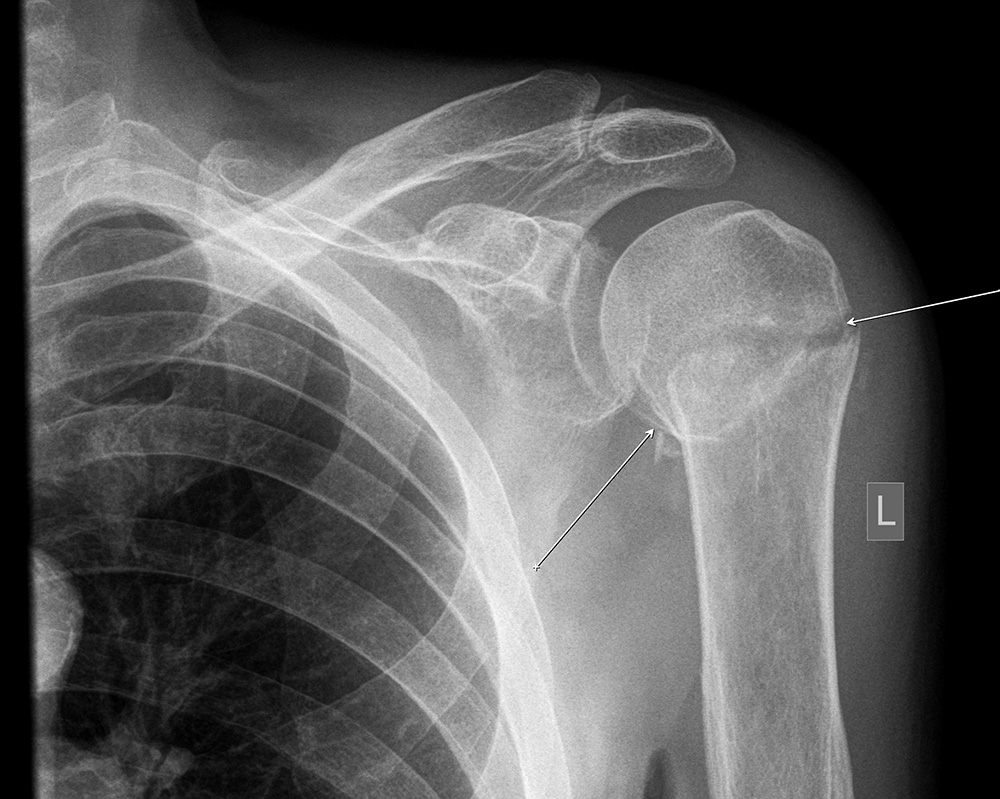

На Р-грамме левого плечевого сустава в 2-х проекциях - межсуставная щель несколько расширена, головка плечевой кости с ровными контурами, смещена несколько кнаруже, имеется перелом в области шейки плечевой кости со смещением костных отломков.